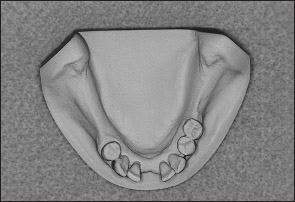

Fig 1-12 Mandibular Kennedy Class I arch.

Fig 1-14 Mandibular Kennedy Class II arch.

Fig 1-16 Mandibular Kennedy Class III arch.

Fig 1-18 Mandibular Kennedy Class IV arch.